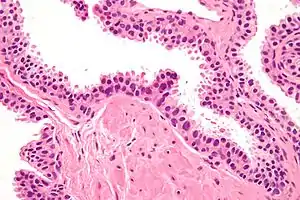

| Micrograph showing high-grade prostatic intraepithelial neoplasia. H&E stain. | |

High-grade prostatic intraepithelial neoplasia (HGPIN) is an abnormality of prostatic glands and believed to precede the development of prostate adenocarcinoma (the most common form of prostate cancer).[1][2]

It may be referred to simply as prostatic intraepithelial neoplasia (PIN). It is considered to be a pre-malignancy, or carcinoma in situ, of the prostatic glands.

Histology

HGPIN typically has one of four different histologic patterns:[2]

- tufted (fascicular patterning)

- micropapillary,

- cribriform and,

- flat.

Its cytologic features are that of prostatic adenocarcinoma:

- presence of nucleoli,

- increased nuclear-to-cytoplasmic ratio and,

- increased nuclear size.

Microscopically, PIN is a collection of irregular, atypical epithelial cells. The architecture of the glands and ducts remains normal. The epithelial cells proliferate and crowding results in a pseudo-multilayer appearance. They remain fully contained within a prostate acinus (the berry-shaped termination of a gland, where the secretion is produced) or duct. The latter can be demonstrated with special staining techniques (immunohistochemistry for cytokeratins) to identify the basal cells forming the supporting layer of the acinus. In prostate cancer, the abnormal cells spread beyond the boundaries of the acinus and form clusters without basal cells. In HGPIN, the basal cell layer is disrupted but present. PIN is primarily found in the peripheral zone of the prostate (75-80%), rarely in the transition zone (10-15%) and very rarely in the central zone (5%), a distribution that parallels the zonal distribution for prostate carcinoma.[6]